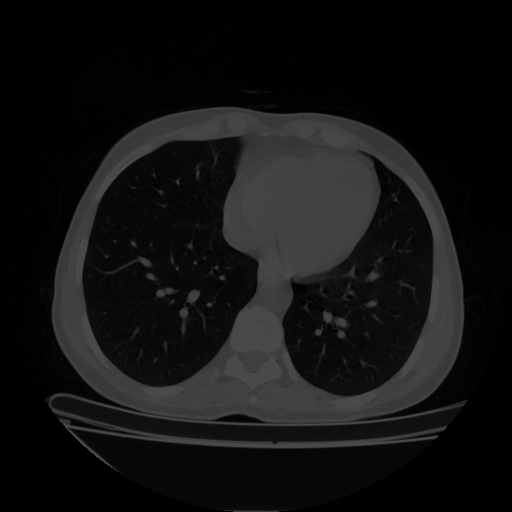

Original VENOUS CT scan

No window - Raw intensity values

Lung window (WL -600, WW 1500 β†’ Low βˆ’1350, High +150)

Mediastinum window (WL 40, WW 400 β†’ Low βˆ’160, High +240)